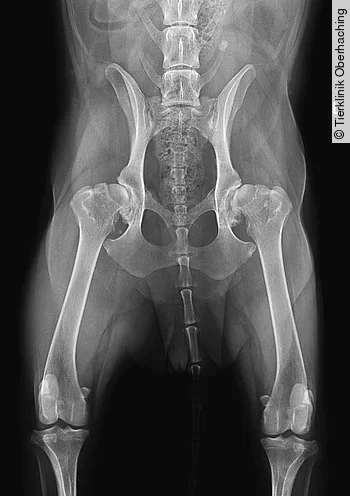

Bei einem dysplastischen Gelenk werden durch die nach dorsal gerichtete Subluxationstendenz der mediale Anteil des Femurkopfes sowie der dorsale Acetabulumrand überlastet, sodass deren Ossifikation verzögert ist [6], während der ventromediale Anteil des Acetabulums und der laterale Anteil des Femurkopfes zu früh ossifizieren [7]. Hieraus resultieren eine Abflachung des Acetabulums sowie eine Unterentwicklung des dorsalen Acetabulumrandes [13]. Die Knorpelflächen werden in den überlasteten Regionen abgerieben, bis subchondraler Knochen freiliegt, der als Reaktion vermehrt sklerosiert [7]. [Abb. 1] zeigt die weit fortgeschrittenen degenerativen Veränderungen der HD eines älteren Patienten. Im Vergleich hierzu bildet [Abb. 4 b] die initiale Subluxationstendenz eines jung adulten Hundes vor der Entstehung degenerativer Veränderungen ab. Die ausgeprägte Coxarthrose in [Abb. 1] ist als Folge der Laxizität und Inkongruenz der Hüftgelenke zu werten. Grundsätzlich können degenerative Veränderungen des Hüftgelenks auch z. B. infolge eines Traumas (Luxation, Fraktur), Osteochondrose o. ä. ohne zugrundeliegende HD entstehen [14].

Die Bemuskelung der Hintergliedmaßen ist bei Hunden mit HD (z. B. beim Deutschen Schäferhund) im Vergleich zu nicht-dysplastischen Hunderassen wie z. B. dem Greyhound deutlich geringer ausgeprägt. Hierbei wirkt sich sowohl die Rassezugehörigkeit zum Deutschen Schäferhund als auch das Vorhandensein einer HD negativ auf die Muskelmasse aus [54]. [Abb. 2] zeigt einen Deutschen Schäferhund mit sehr deutlicher Ausprägung einer beidseitigen HD.